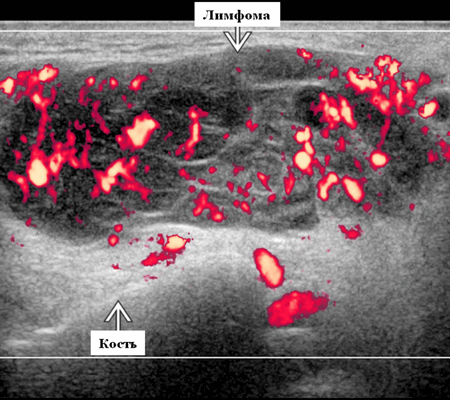

- Узловая неходжкинская лимфома (НХЛ): одиночные или множественные увеличенные яйцевидные внутрипаротидные лимфатические узлы, которые на УЗИ гомогенно гипоэхогенны по отношению к паренхиме околоушной железы, эхо-картина сетчатая. Заднее акустическое усиление. Выраженная внутриузловая гиперваскуляризация

Лучший диагностический признак на УЗИ при узловой НХЛ: множественные однородные, четко выраженные образования околоушных желез и лимфаденопатия верхних отделов шеи. Паренхиматозная НХЛ: инфильтративная околоушная опухоль, фон СШ, BLEL

Цветной допплер. Узловая НХЛ. Выраженная центральная или внутриузловая гиперваскуляризация. Паренхима при неходжкинской лимфоме более диффузная железистая гиперваскуляризация. Васкуляризация от умеренной до выраженной в плохо очерченных образованиях.